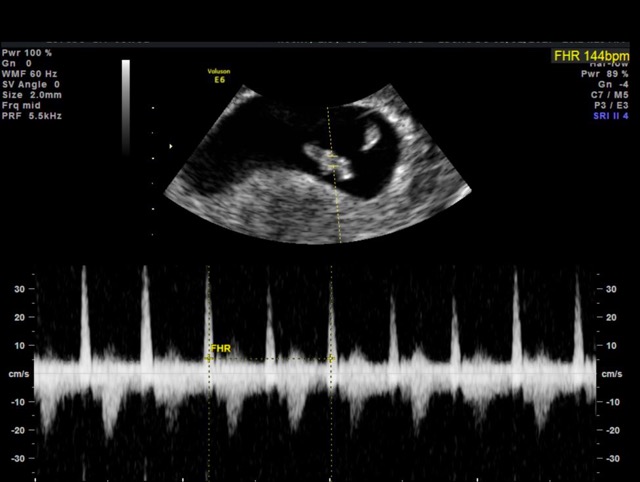

Ultrasound

Today was my first ultrasound and i found out im actually further along than I thought. I'm 7 wks and 5 days now and our little sweet pea has a strong heartbeat.